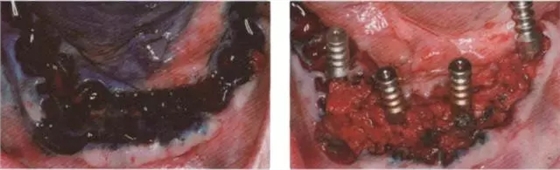

圖10 在序列拔牙后及用生理益水中洗之前應(yīng)用光敏劑 (HELB0, bredent medlcal公司).

圖11 在手術(shù)快結(jié)束時放置印模t注用于制作即刻臨時修復(fù)體